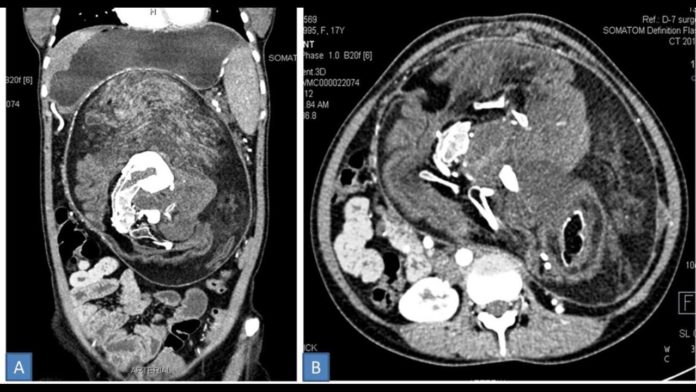

Η νεαρή υποβλήθηκε σε χειρουργική επέμβαση και οι γιατροί εντόπισαν στο σώμα της μία μάζα 35 εκατοστών εντός της οποίας υπήρχαν οστά, δόντια, μαλλιά και «άλλα μέλη», όπως αναφέρουν οι πληροφορίες του Newsweek.

Οι εξετάσεις έδειξαν πως η μάζα προκαλούσε προβλήματα σε όλη την κοιλιακή χώρα της νεαρής, ενώ στην αξονική τομογραφία εμφανίστηκε κάτι που έμοιαζε με πλευρά και νευρώσεις.

Η μάζα που έβγαλαν οι γιατροί από την 17χρονη είναι η μεγαλύτερη που έχει εντοπιστεί ποτέ σε ανάλογη περίπτωση.